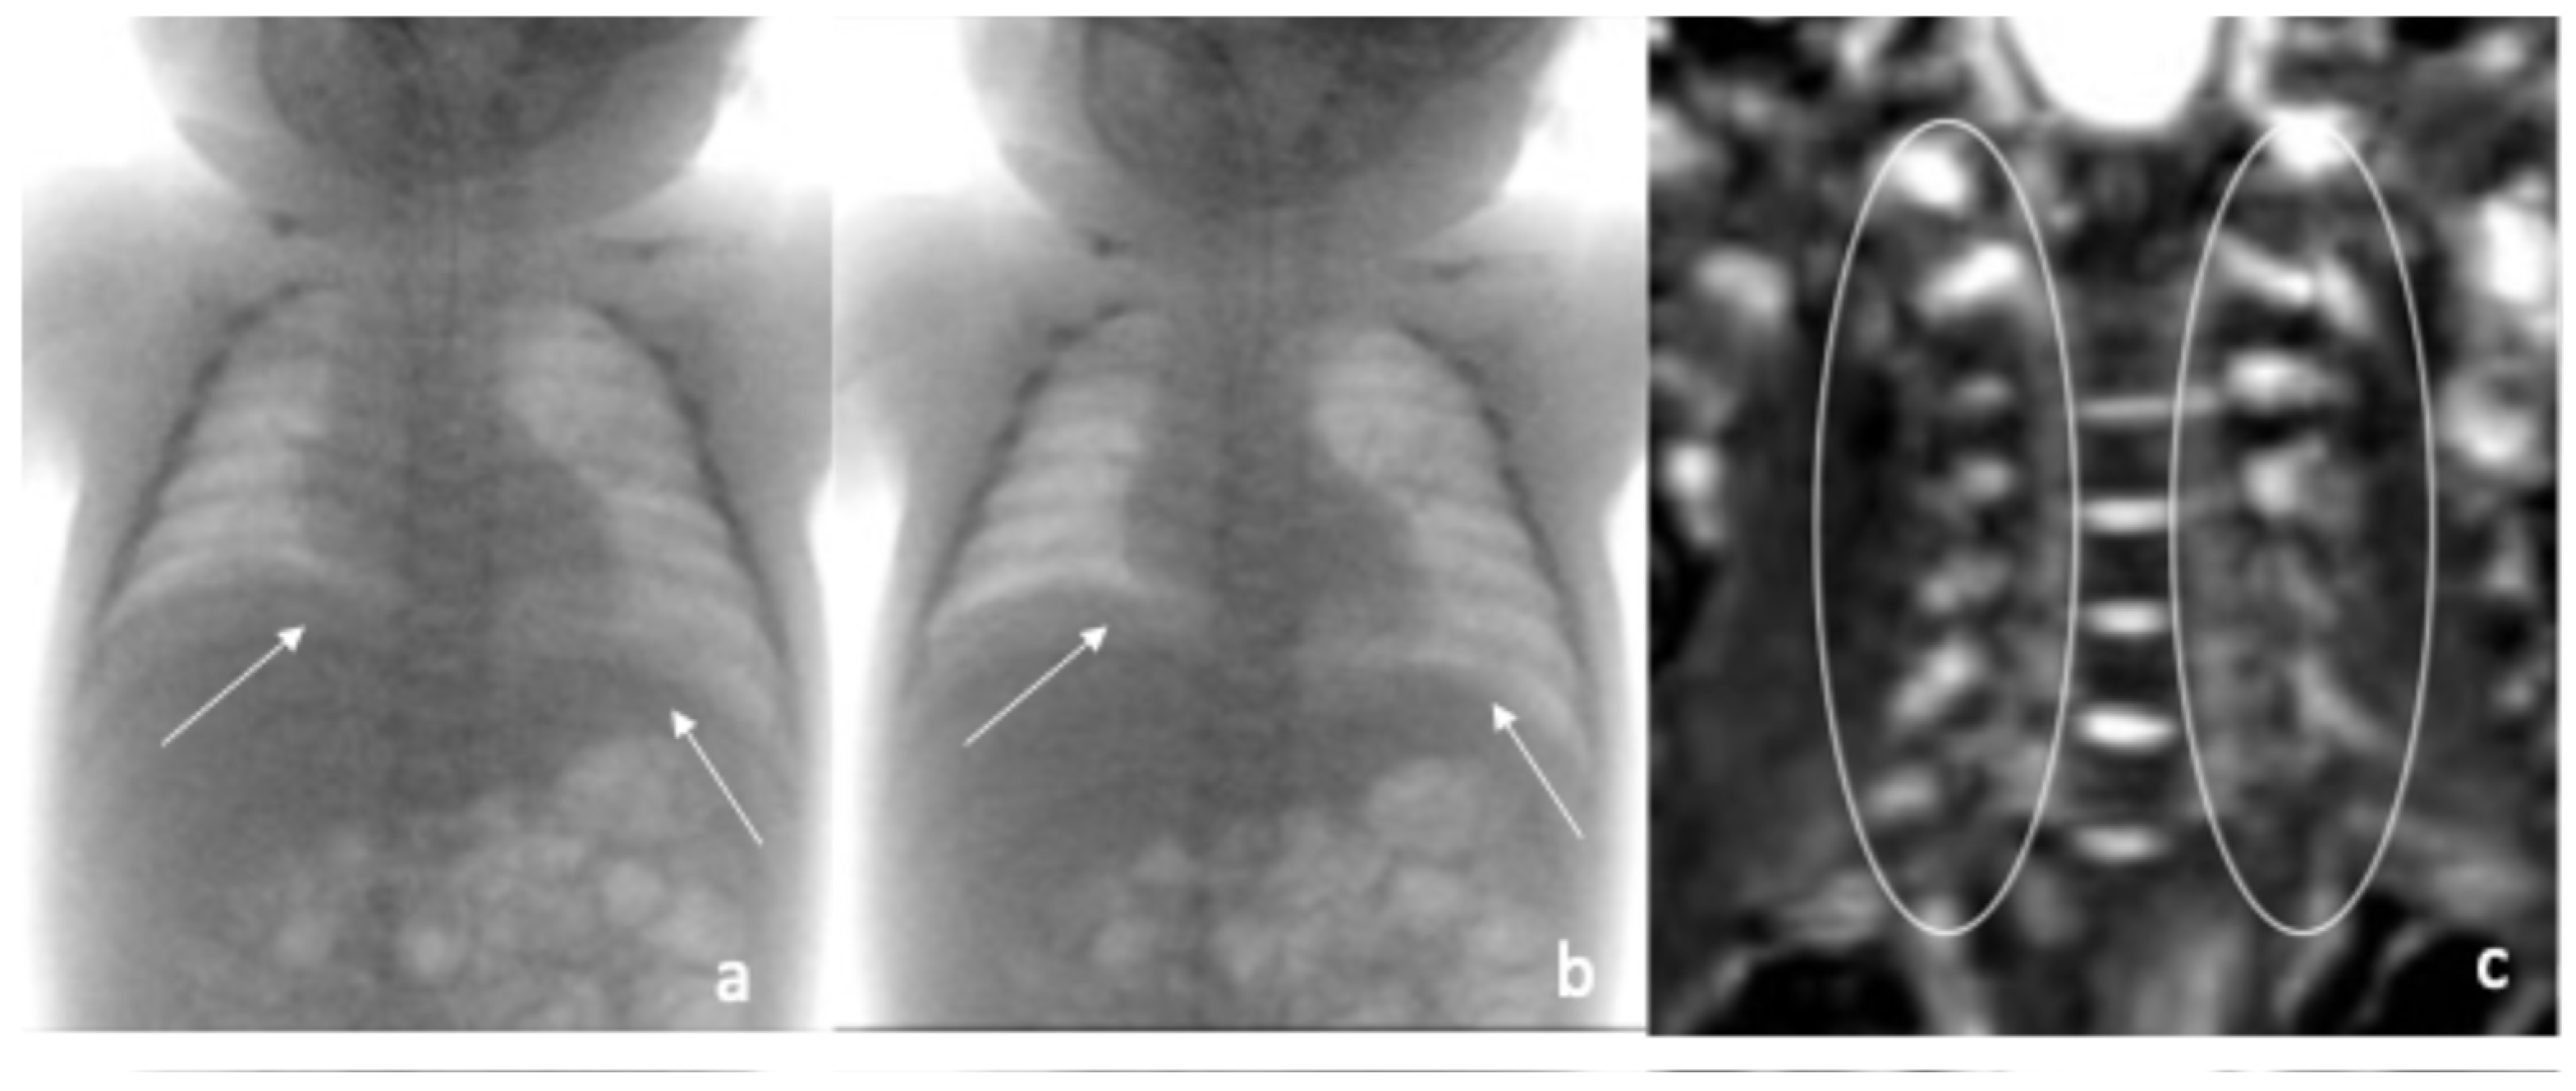

| Fluoroscopic evaluation | Inadequate bilateral diaphragm excursion | Reduced diaphragmatic excursion |

| Magnetic Resonance Imaging (MRI) | Normal root courses of brachial plexus bilaterally | Normal MRI of the brain and spinal cord |